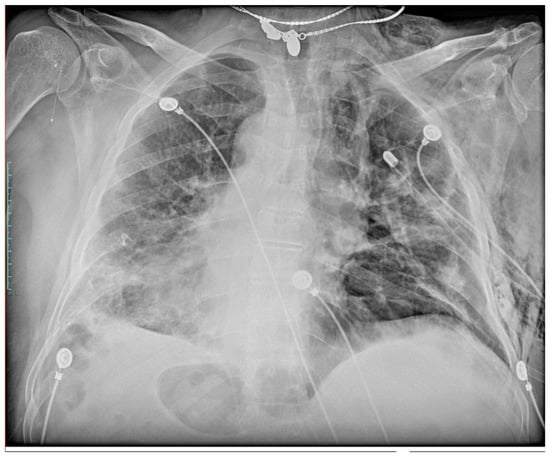

Pneumomediastinum and Pneumothorax as Relevant Complications of Sub-Intensive Care of Patients with COVID-19: Description of a Case Series

2. Description of Cases